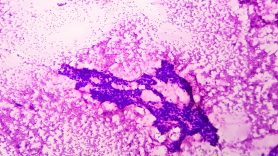

Poly-ADP ribose polymerase (PARP) inhibition previously was shown to be particularly effective in cancers harboring gene mutations that negatively affect DNA repair, such as BRCA1/2 mutations, because these cancers rely even more than others on PARP proteins to repair any DNA damage. By inhibiting PARP proteins, these cancers are unable to repair their DNA, leading to an inability to replicate and, ultimately, cell death.